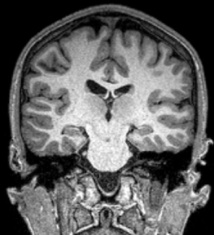

Como explica el Instituto Douglas en una nota de prensa, nuestro ciclo cotidiano de sueño-vigilia se rige por un temporizador interno de 24 horas, el reloj circadiano. Sin embargo, hay pruebas de que la actividad diaria también está influenciada por ritmos mucho más cortos, que son conocidos como ritmos ultradianos y siguen ciclos de cuatro horas.

Estos ritmos ultradianos de cuatro horas se activan por la dopamina, una sustancia química clave en el cerebro. Cuando los niveles de dopamina se desbaratan -como se cree que es el caso de las personas que sufren enfermedad bipolar o esquizofrenia- los ritmos de cuatro horas se pueden estirar hasta 48 horas.

Con este estudio, realizado en ratones modificados genéticamente, Storch y su equipo demuestran que las alteraciones del sueño, que en el pasado han sido asociadas con la alteración del ritmo circadiano, son en realidad el resultado de un desequilibrio de un generador (oscilador) de ritmo ultradiano basado en dopamina.

Los hallazgos del equipo también ofrecen una explicación muy específica para el ciclo de dos días entre manía y depresión observado en ciertos casos bipolares: es un resultado del oscilador de dopamina ejecutándose en un ciclo de 48 horas.

Este trabajo es innovador no sólo por su descubrimiento de un nuevo generador de ritmo a base de dopamina, sino también a causa de sus vínculos con la psicopatología. Estos nuevos datos sugieren que cuando el oscilador de excitación ultradiana se desvía, el sueño se altera y se produce la manía en pacientes bipolares; el desequilibrio del oscilador puede presumiblemente estar también asociado con episodios esquizofrénicos en personas que padecen ese problema.